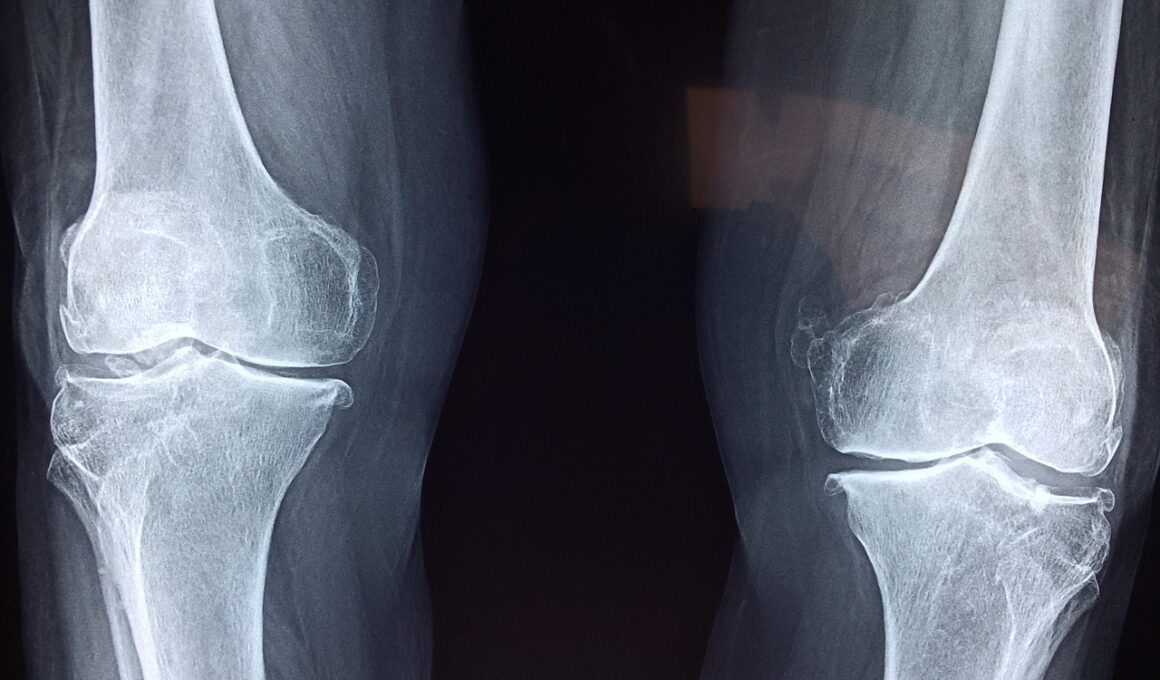

The human body consists of various joints that are essential for movement and overall functionality. Joint health involves maintaining the smooth operation of these connections, supported by cartilage, ligaments, tendons, and synovial fluid. Factors contributing to joint deterioration include age, obesity, and sedentary lifestyles. As we age, the cartilage can wear down, leading to conditions like osteoarthritis, which is characterized by inflammation, pain, and decreased mobility. Regular yoga practice can play a substantial role in preventing these issues by enhancing blood flow, which nourishes the tissues around the joints and promotes healing. Furthermore, certain yoga poses encourage strengthening muscles that support the joints, which is essential for stability and preventing injuries. Strengthening these muscles reduces the risk of falls and strains, making daily activities more manageable. Additionally, practicing mindfulness can lessen the perception of pain by altering the body’s response to discomfort. Yoga not only helps maintain physical joint health but also enhances emotional well-being, providing a holistic approach to joint care. Incorporate joint-focused yoga routines into your wellness regimen for better mobility as you navigate through life.